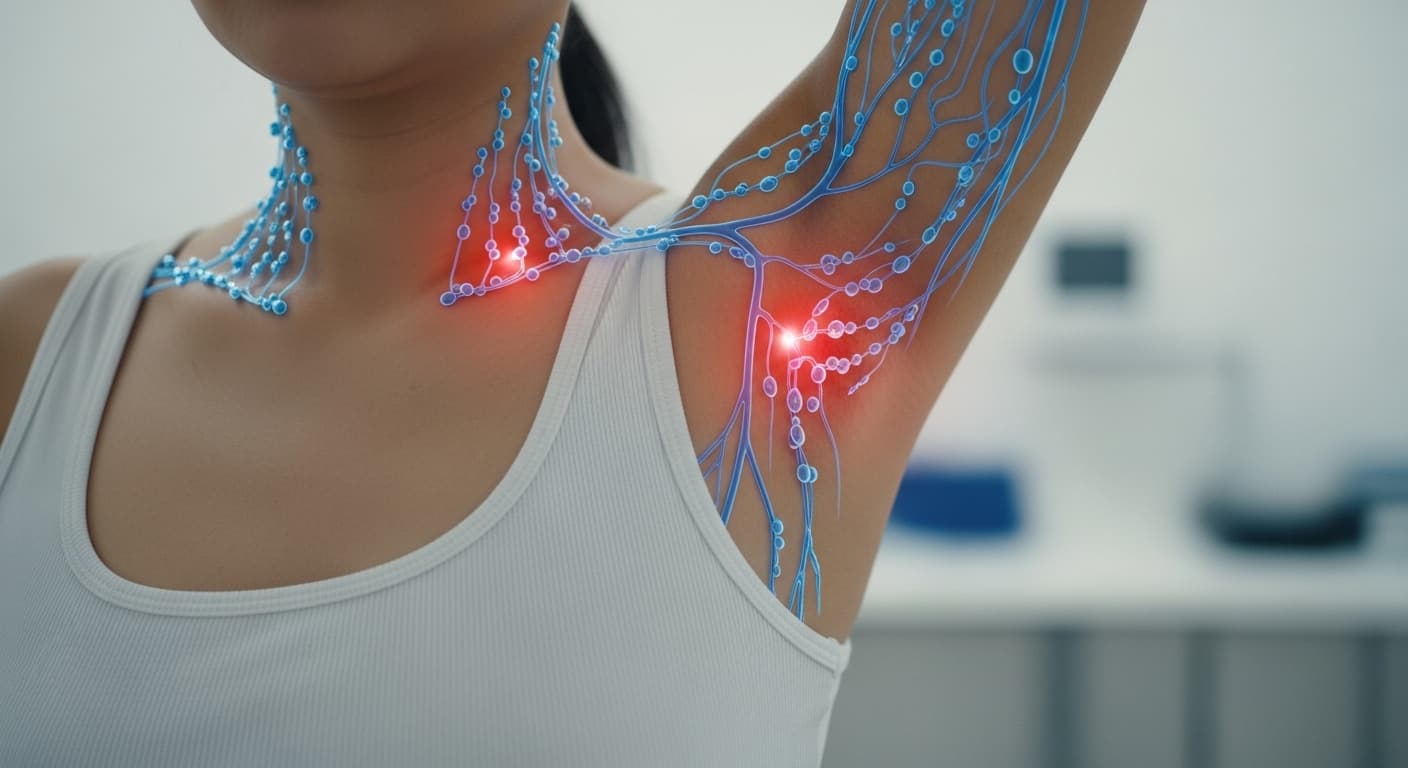

스트레스, 잘못된 자세, 꽉 조이는 속옷 등은 이러한 림프 순환을 방해하는 주범이 될 수 있어요. 마치 꽉 막힌 하수구처럼, 림프액이 제대로 흐르지 못하면 유방 조직과 주변 부위에 노폐물과 수분이 정체되면서 묵직함, 붓기, 그리고 통증으로 이어지게 된답니다. 특히 여성의 경우, 월경 주기 전후로 에스트로겐과 프로게스테론의 변화가 유방 조직의 수분 저류를 유발하고 민감도를 높여 림프 순환 저하와 시너지를 내면서 증상을 악화시킬 수 있어요. 이 호르몬 변화는 유방 내의 혈관 투과성을 증가시켜 조직액이 더 쉽게 축적되도록 만들죠.

또한, 만성적인 염증 반응도 가슴 통증의 중요한 원인이 될 수 있어요. 미세한 염증들이 림프관의 기능을 저하시키고, 주변 조직에 부종을 일으키면서 통증 수용체를 자극하게 됩니다. 현대인에게 흔한 자율신경계 불균형도 빼놓을 수 없어요. 스트레스로 인해 교감신경이 과도하게 활성화되면 혈관이 수축되고 미세 순환이 저해되어 림프 흐름이 더욱 나빠질 수 있거든요.

샤워 후 로션을 바를 때, 유방 주변부터 겨드랑이, 쇄골까지 손가락 지문 부위로 원을 그리듯 부드럽게 마사지해주세요. 절대로 세게 누르지 말고, 피부를 쓸어주듯이 가볍게 쓰다듬는 것이 중요해요. 막힌 길을 부드럽게 열어주는 느낌으로요.